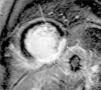

O ETT, realizado a 28 de janeiro de 2010, mostrou espessamento de ambos os folhetos e uma massa hiperecogénica e homogénea de reduzidas dimensões (0,8x0,9cm) na vertente auricular do folheto posterior da válvula mitral (VM), regurgitação mitral ligeira, ventrículo esquerdo moderadamente dilatado e com alterações da motilidade segmentar (acinésia dos segmentos basais e médios das paredes inferior e inferolateral, hipocinésia dos segmentos apicais da parede inferoseptal), com depressão moderada a grave da função sistólica global: fração de ejeção de 34% por método de Simpson biplano. O ETE, realizado no mesmo dia, permitiu excluir outras fontes cardioembólicas e caracterizar a massa da VM, que se apresentou séssil, de bordos irregulares mas bem definidos, de ecogenecidade intermédia, heterogénea e móvel acompanhando os movimentos do folheto (Figura 1). Não foi identificado contraste espontâneo nas cavidades esquerdas.

Na caracterização da massa, a RM não acrescentou significativamente informação à fornecida pelo ETE, tendo sido este o exame que melhor a permitiu caracterizar. No entanto, a RM identificou a presença de necrose, tendo sido útil para o diagnóstico de enfarte evoluído na sequência de episódio de dor torácica decorrida em meio extra‐hospitalar e num jovem.